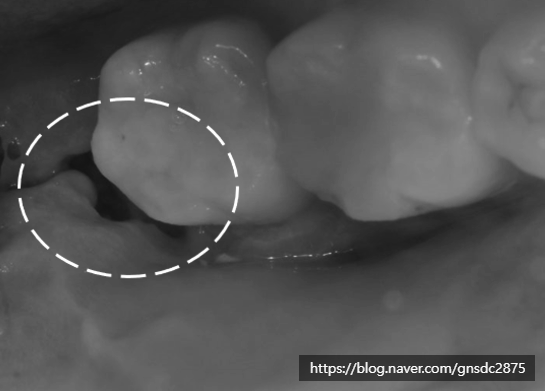

사랑니 발치 후 피덩이(혈병)

많은 분들이 빈공간 안에 있는

피딱지, 피덩이를 보고 떼어내야 하나 생각하십니다.

그러나 이 피덩이 또한 회복하는 과정 중

발치 후 초기에 자연스럽게 형성되는 혈병(혈전)으로,

출혈을 막고 상처를 보호하는 역할을 합니다.

피덩이(혈병)이 표시되어 있다.